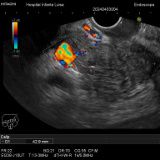

Enfermedades relacionadas con la vesícula y vías biliares

Colelitiasis

Coledocolitiasis

Pólipos vesiculares